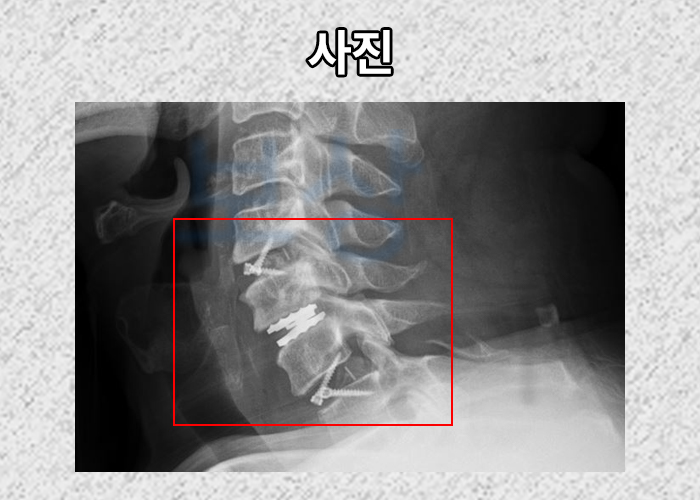

위 진단서를 보시면 윤@@님은 **경추골절 S1290 **진단받아 경추 전후방고정술을 받을 수 밖에 없었습니다.

사실 큰 수술을 하셨음에도 척수 손상으로 인해 팔 다리가 저리고 마비 증세를 호소하셨죠. 윤@@님은 억울하게 남게 되는 후유증을 올바로 보상받고 싶으셨기 때문에 보상파트너 산재노무팀으로 연락주셨습니다.

위와 같은 검사를 요청하고 올바른 장해 평가를 위해 도움을 드린 결과 윤@@님은 산재 장해등급 9급 15호 인정받아 장해급여 55,663,630원 지급받으실 수 있었습니다.